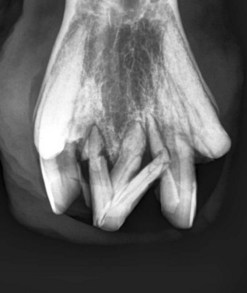

image image image

Fig. 13.37 (A) Maxillary cheek tooth row of a miniature Shetland pony with marked dysplasia of the 109, 110, and 111 and a corresponding wave mouth on the mandibular row. (B) Markedly enlarged, radiodense, dysplastic 110, which has displaced the reserve crowns and apices of 111 and 109 caudally and rostrally, respectively. (C) Abnormally small 302. The deciduous 702 remnant is retained (arrow).